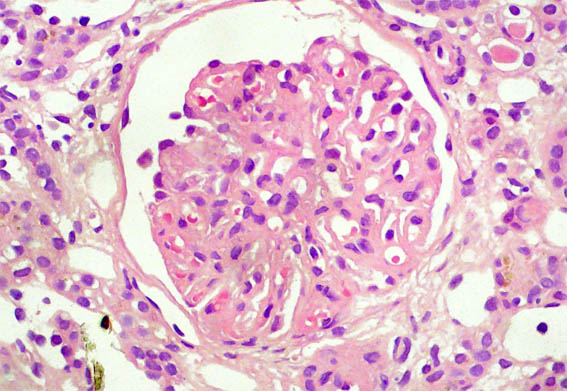

Figura 1.

H&E, X100.